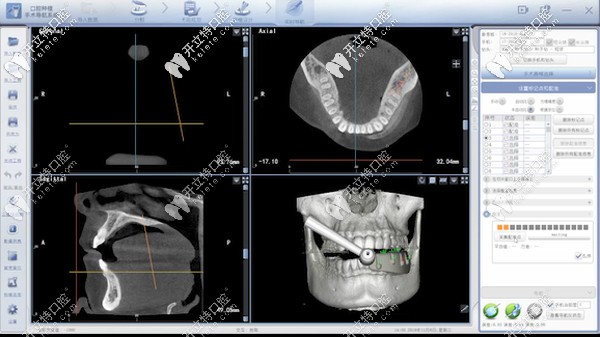

據(jù)了解:口腔種植數(shù)字化動(dòng)態(tài)導(dǎo)航是種植牙當(dāng)中的黑科技,主要通過(guò)計(jì)算機(jī)重建患者口腔頜骨三維立體模型。

數(shù)字化動(dòng)態(tài)導(dǎo)航種植技術(shù)

它就像汽車導(dǎo)航一樣,通過(guò)顯示屏實(shí)時(shí)直觀地看到種植體植入頜骨的全過(guò)程,全程監(jiān)控種植位點(diǎn)、角度、深度。

能夠避免損傷重要的解剖結(jié)構(gòu),給患者提供更加安全、精準(zhǔn)、高效的體驗(yàn)。